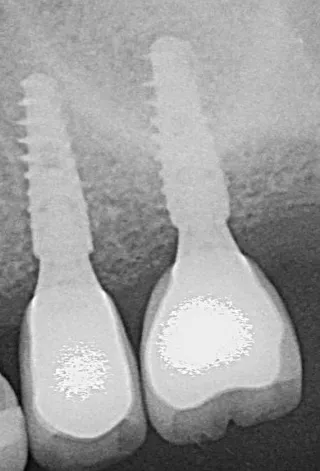

Therefore, we opted for a shortened dental arch that would replace 25 and 26 but not 27. We decided to perform simultaneous sinus floor augmentation and implant placement, as there was only 4 mm of native bone at the implant sites.

1-2. Panoramic radiography and cone-beam computed tomography showing vertical bone loss. With only 4 mm of sinus floor bone, implant placement was not feasible.